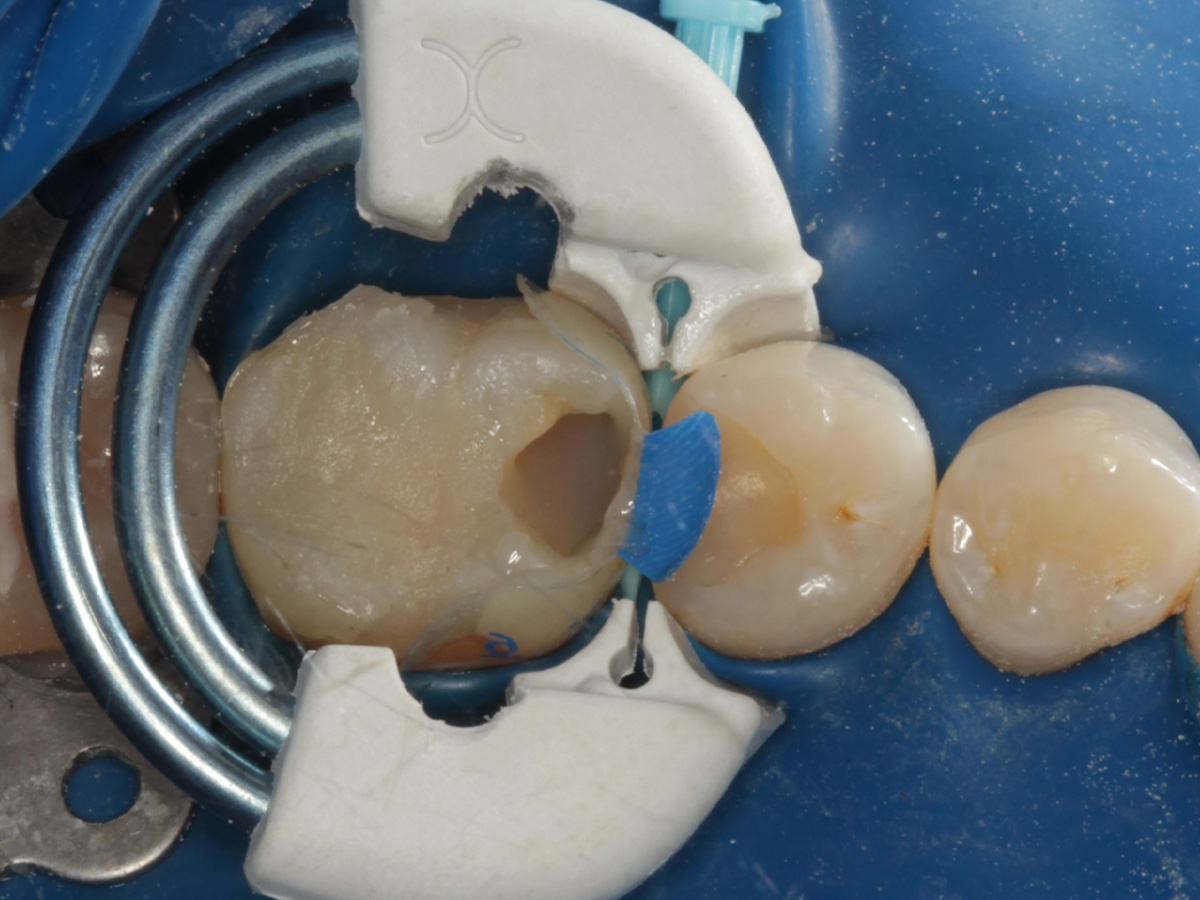

Abbildung 10

Height Indicator vor Auswahl der passenden Evolve Matrize distal

Abbildung 11

Height Indicator vor Auswahl der passenden Evolve Matrize mesial

Abbildung 12

Applikation der Matrizen: Evolve Blau Molar 5 mm distal und 6 mm mesial